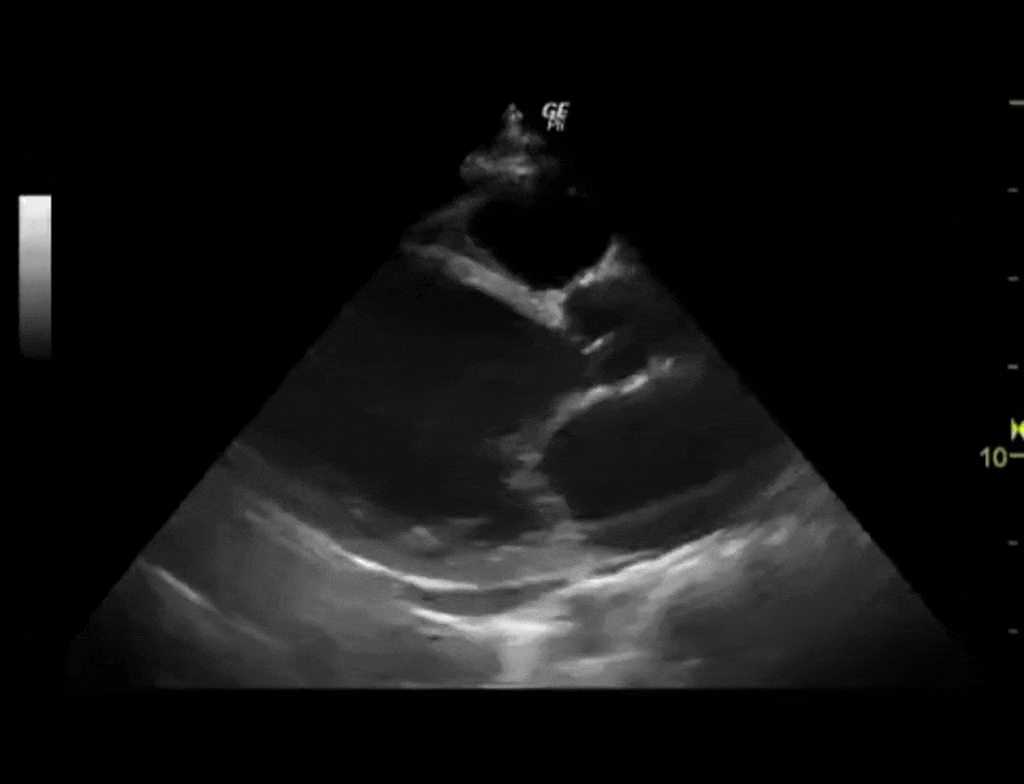

Echocardiogram cardiomyopathy intensive